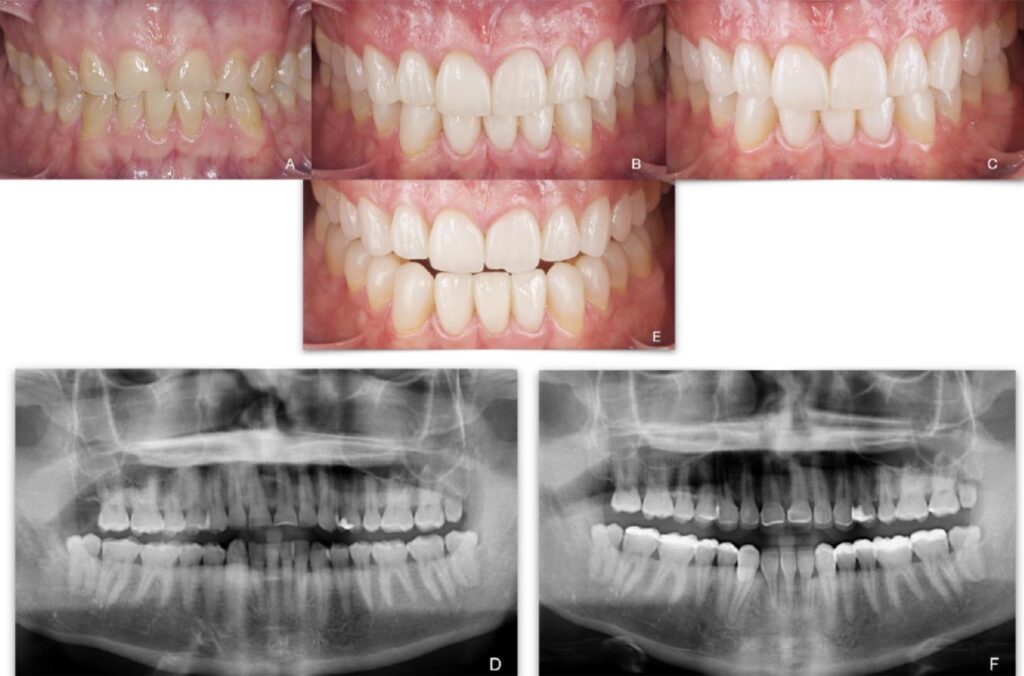

Figure 4. Patient 4: Generalized severe pathological tooth wear (TWES 2.0). (A) Intraoral situation: inverted

occlusal plane shown for a patient with extremely worn anterior teeth associated with a compensatory

extrusion of the mandibular anterior teeth. (B) Occlusion after treatment, highlighting aesthetic

and functional improvement. (C) A 5-year follow-up photograph showing excellent periodontal health

with the total absence of recession, highlighting the maintenance of occlusal contact relationships.

(D) Initial orthopantomography. (E) Final orthopantomography showing the supplementation of

all teeth without endodontic treatments. Felspathic vestibular veneers from 1.2 to 2.2, CAD-CAM

nanoceramic resin palatal veneers from 1.3 to 2.3, and occlusal and vestibular veneers on 1.5, 1.4, 2.4

and 2.5. Finally, lithium disilicate veneers from 3.5 to 4.5 and 3.7, 4.7.

Figure 5. Patient 5: Generalized severe pathological tooth wear (TWES 2.0). (A) Intraoral situation:

edge-to-edge bite and occlusal relationships shown by a patient with severely worn anterior teeth,

(B) Intraoral appearance at 1 year. The aesthetic and functional improvement is remarkable, although

there is considerable plaque accumulation. (C) Follow-up photograph at 5 years, showing acute

gingivitis, which was treated successfully with a tartrectomy and the reinforcement of hygienic measures.

(D) Initial orthopantomography. (E) Final orthopantomography showing the supplementation

of all teeth. Lithium disilicate veneers from 1.4 to 2.3, CAD-CAM nanoceramic palatal veneers from

1.3 to 2.3, occlusal and vestibular direct composites on 1.5 and 2.5. Lithium disilicate veneers from

3.2 to 4.2, direct stamped composite resin in the posteroinferior sectors (3.3–3.4 and 4.3–4.7). One

implant in 1.5 and the change of the prosthesis on implants 3.5 and 3.6 can be noted. Finally, we must

mention a root canal treatment applied the teeth that had previous crowns.

Figure 6. Patient 6: Generalized severe pathological tooth wear (TWES 2.0). (A) Intraoral situation:

edge-to-edge bite and occlusal relationships shown by a patient with severely worn anterior teeth.

A compensatory extrusion of the mandibular teeth can be appreciated (B) Occlusion after treatment,

showing considerable esthetic and functional improvement. (C) Follow-up photograph at 5 years

just after bicarbonate spray treatment, showing the maintenance of periodontal health at 5 years.

(D) Initial orthopantomography. (E) Final orthopantomography showing facial veneers from 1.6 to

2.6 and free-hand direct composites in the mandible (3.6–4.6).